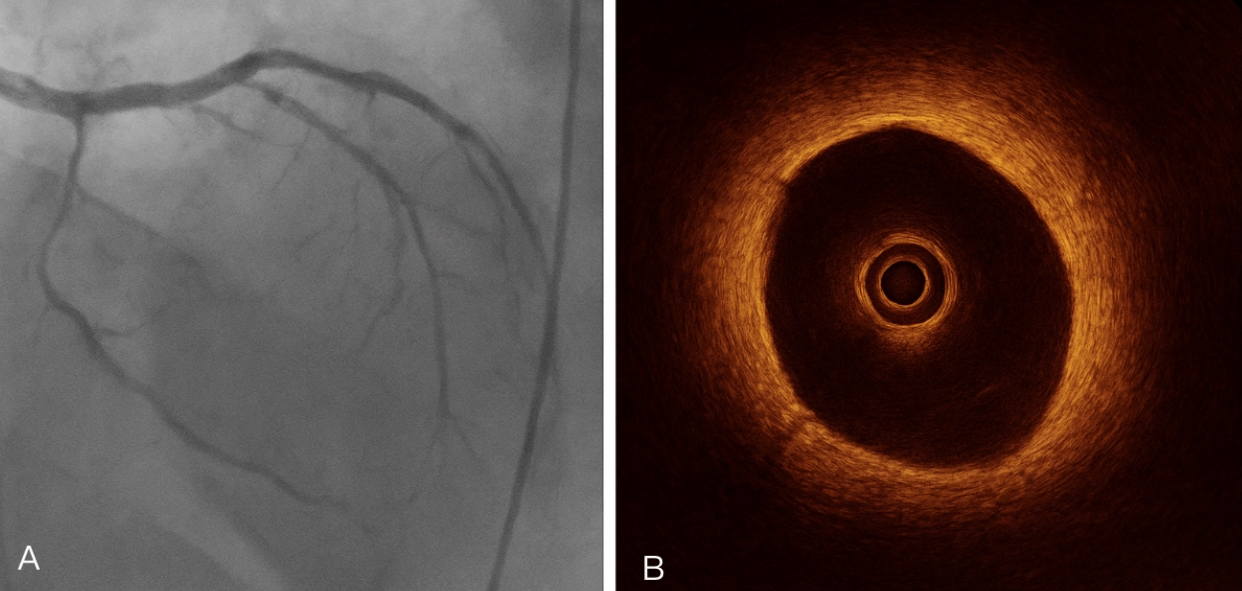

Emergent coronary angiography revealed a long, diffuse narrowing of the mid-left anterior descending (LAD) artery with preserved distal flow (Thrombolysis in Myocardial Infarction [TIMI] grade 3) and no evidence of atherosclerotic plaque or thrombus (Figure 2A). Optical coherence tomography confirmed the presence of an intramural hematoma and intimal flap, establishing the diagnosis of spontaneous coronary artery dissection (SCAD) (Figure 2B). The patient remained hemodynamically stable with no ongoing chest pain.

Coronary angiography is performed as a first-line diagnostic tool, particularly in the presence of ST-segment elevation. However, certain SCAD lesions, such as those classified as type 3,10 could mimic atherosclerosis with focal or tubular stenosis. Therefore, advanced intravascular imaging techniques such as optical coherence tomography (OCT) and intravascular ultrasound (IVUS) are essential, as diagnosis can be made even with intimal flaps and/or intramural hematoma being present.11 In our case, optical coherence tomography provided definitive evidence of SCAD, guided a conservative strategy, and helped to avoid unnecessary PCI.